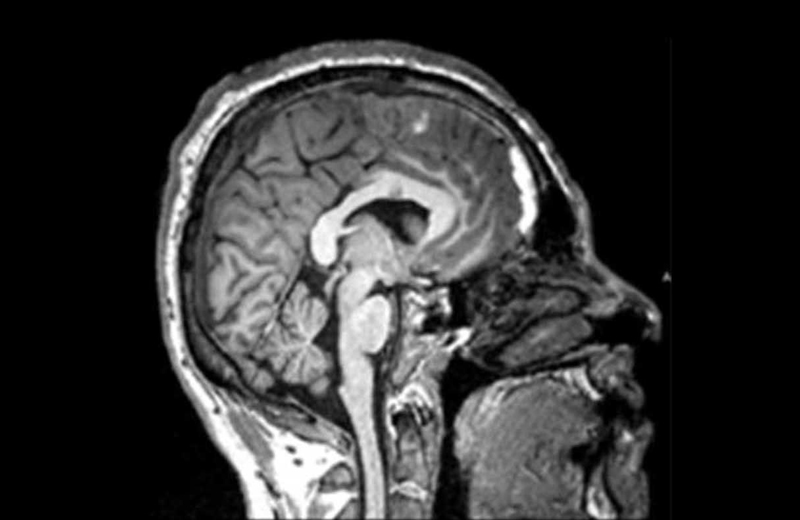

Another study that could help identify patients for the current trial showed that patients with certain patterns of injury that are visible on their CT scans were less likely to make a complete recovery a year later.

Trial participants must enroll on the day of their injury, so they can be treated promptly. They must have a CT scan showing evidence of bleeding, and a blood test and exam that indicate moderate to mild TBI.